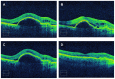

Figures